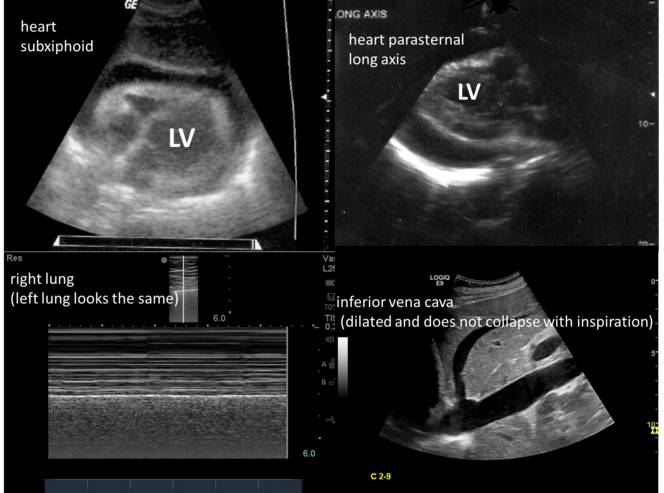

This 67 y/o male with known lung cancer presents with hypotension. His heart (subxiphoid and parasternal long views), lung, and inferior vena cava images are shown. For the lung images, the same findings are present on both left and right sides throughout the entire lung fields. What is the most likely cause of his hypotension?

Note: The images are likely hard to see, but there’s an awful lot of black around the heart and the lungs on ultrasound.

Answer: cardiac tamponade

Explanation: The ultrasound images show a pericardial effusion and a dilated inferior vena cava; this combined with the patient history are most consistent with cardiac tamponade. There is normal pleural sliding (sand on the seashore sign, eg – no pneumothorax), so this is not tension pneumothorax. With septic shock or hypovolemic shock, the IVC will be small.